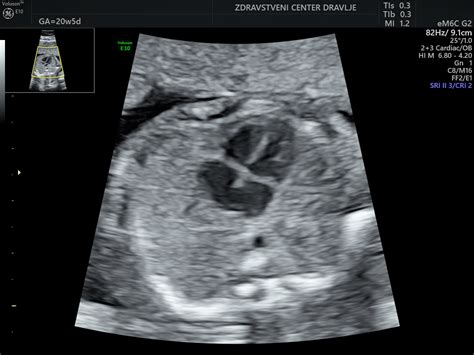

Natančna UZ ocena morfologije ploda je ena od najpomembnejših preiskav v nosečnosti, običajno opravljena med 20. in 22. tednom nosečnosti (nekatere smernice navajajo tudi med 19. in 23. tednom). Namenjena je predvsem potrditvi normalnega razvoja ploda oziroma odkrivanju večjih razvojnih nepravilnosti ter t.i. "mehkih" označevalcev, ki povečajo tveganje za prisotnost kromosomske napake pri plodu. V tem času je razvoj plodovih organov večinoma že zaključen, kar z veliko verjetnostjo omogoča napoved rojstva zdravega otroka.

Med morfologijo se natančno pregledajo vsi organski sistemi ploda: glava, možgani, obraz (vključno z izključitvijo zajčje ustnice), hrbtenica, srce, pljuča, prepona, želodec, ledvički, sečni mehur, sprednja trebušna stena, okončine (preštejejo se prstki na rokah in nogah). Pregleda se tudi lega posteljice, število žil v popkovnici in oceni količina plodovnice. V primeru normalnega izvida se lahko z veliko verjetnostjo napove rojstvo zdravega otroka. Izjema so pljuča in možgani, katerih razvoj se nadaljuje tudi po rojstvu, zato je nevrološka ocena ploda nekoliko manj zanesljiva. V tem času se lahko spremeni predviden datum poroda (PDP), če se rast ploda ne ujema s pričakovanji. Na željo se lahko določi tudi spol otroka.